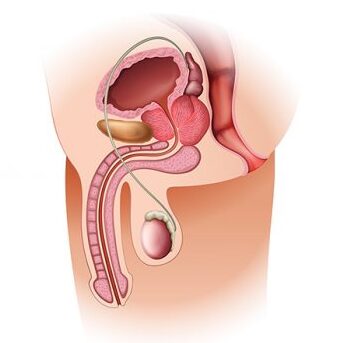

The three systems of an erection

For an erection to happen — and stay — three systems have to work together:

Blood flow in – arteries must open wide enough to flood the penis with blood.

Blood stay – tiny valves in the veins must lock shut, trapping the blood inside.

Signals from the brain – nerves must fire clearly, telling the body “now is the time.”

When these three align, you get a natural, reliable erection.

When even one fails… firmness collapses.

How they break down

Damaged blood vessels: age, stress, high cholesterol or diabetes narrow the arteries, starving the penis of blood.

Weak valves: veins can’t hold the pressure, so the blood escapes within minutes.

Silent nerves: after surgery, illness, or simply time, the nerves go numb, cutting off the vital signal from the brain.